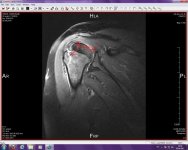

In den sagittalen PD fatsaturierten Aufnahmen erkennt man deutliche Signalalteration im Bereich des Tuberculum majus und im Bereich der Caput humeri lateralseitig betont. In den T2 gewichtigen sagittalen Aufnahmen erkennt man bogenförmige signalarme Linie in Umgebung der Insertion der Supraspinatussehne im Bereich des Tuberculum majus. Kontinuitätserhaltende Darstellung der Supraspinatussehne sowie Infraspinatussehne und des Subscapuiaris. Intakte Darstellung auch Teres major. Intakte Darstellung des Labrum gleneoidale.

Frakturlinie bogenförmig verlaufend im Bereich des Tuberculum majus ohne Dislokation des Fragmentes mit deutlichem umgebenden Knochenödem.